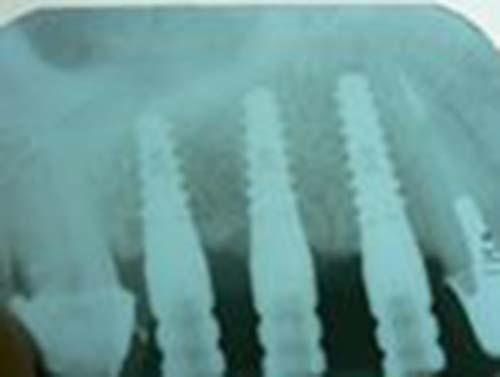

Il nostro studio utilizza strumenti di imaging avanzati, come tomografie e radiografie, insieme a software di progettazione specifici (Nobel Guide), per pianificare interventi estremamente precisi. Questa tecnologia ci consente di eseguire interventi senza tagliare la gengiva, eliminando la necessità di suture e riducendo il tempo di guarigione. Un’innovazione che fa davvero la differenza.